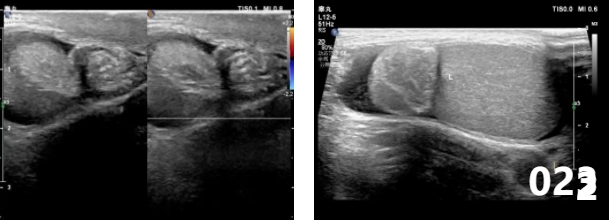

彩色多普勒超声是发现睾丸扭转的首选检查方法。睾丸扭转在超声图像上有一定的特异性,且具有无创、无辐射、价格低廉等优势。